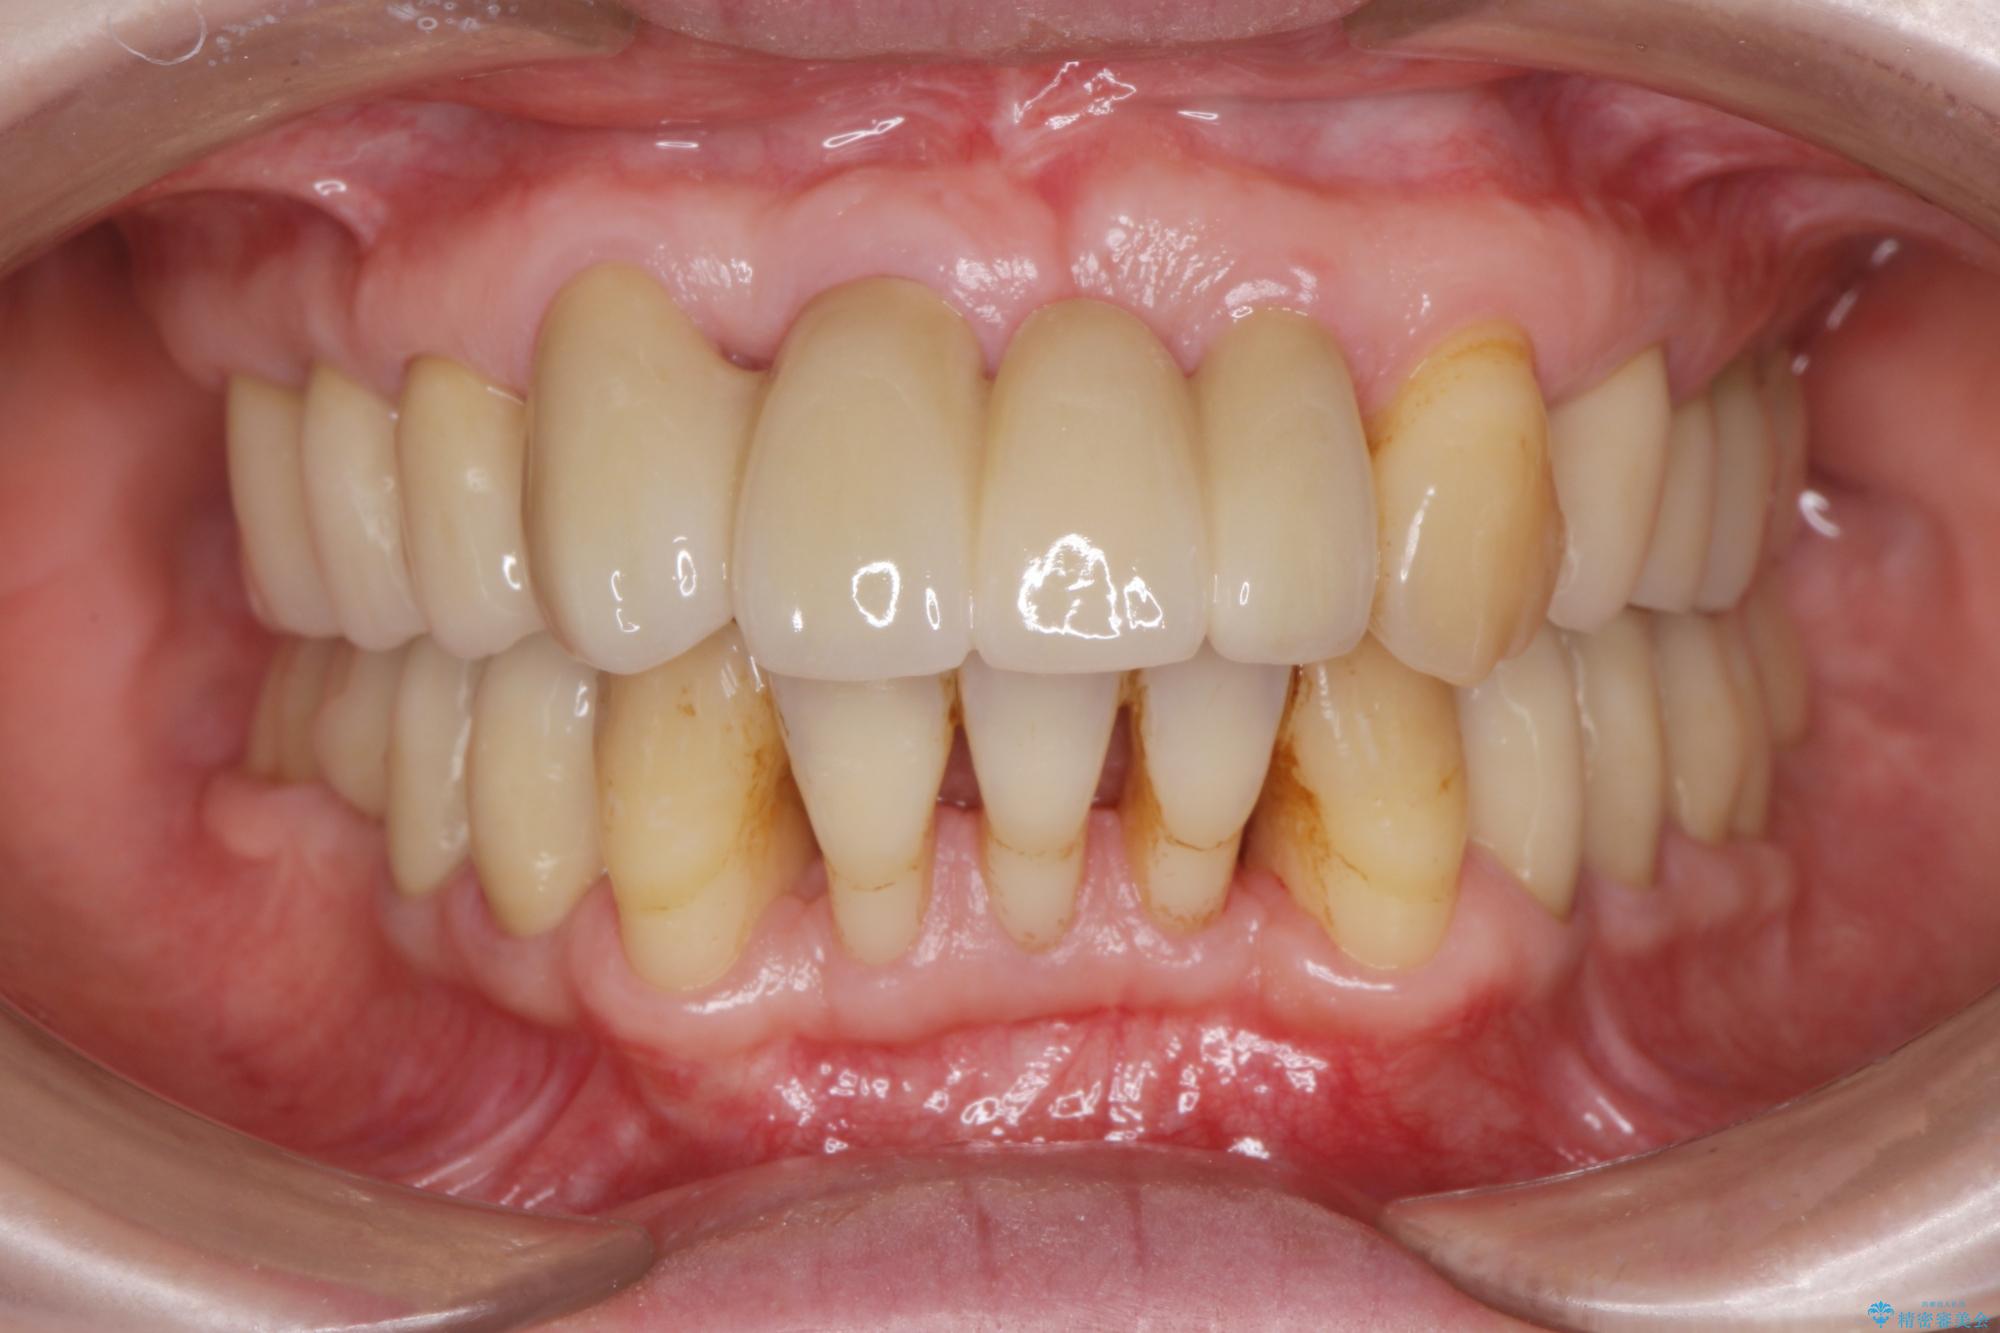

治療前

歯の総合的なマネージメントを行う包括的歯科治療の実践[ 歯周病・矯正・セラミック補綴 ] 治療前画像 歯の総合的なマネージメントを行う包括的歯科治療の実践[ 歯周病・矯正・セラミック補綴 ] 治療前画像 歯の総合的なマネージメントを行う包括的歯科治療の実践[ 歯周病・矯正・セラミック補綴 ] 治療前画像 歯の総合的なマネージメントを行う包括的歯科治療の実践[ 歯周病・矯正・セラミック補綴 ] 治療前画像 歯の総合的なマネージメントを行う包括的歯科治療の実践[ 歯周病・矯正・セラミック補綴 ] 治療前画像 歯の総合的なマネージメントを行う包括的歯科治療の実践[ 歯周病・矯正・セラミック補綴 ] 治療前画像 歯の総合的なマネージメントを行う包括的歯科治療の実践[ 歯周病・矯正・セラミック補綴 ] 治療前画像